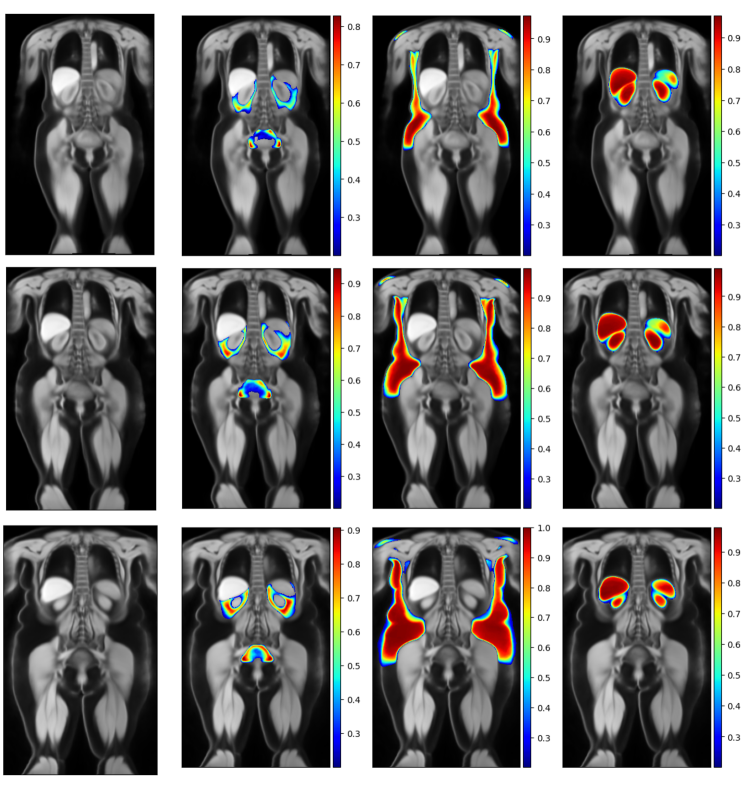

Male Atlases

Figure 8 shows example slices of the female atlases for each category. The figure shows the water-contrast anatomical atlas side by side with the visceral fat label atlas, the subcutaneous fat label atlas, and the abdominal organs label atlas. Each row corresponds to a different BMI group, from normal (first row) to overweight (middle row) to obese (final row). The colour bar represents the probability of the labels.

Refer to caption

Figure 8: Overview of the male atlases for the healthy (first row), overweight (middle row) and obese (last row) groups.